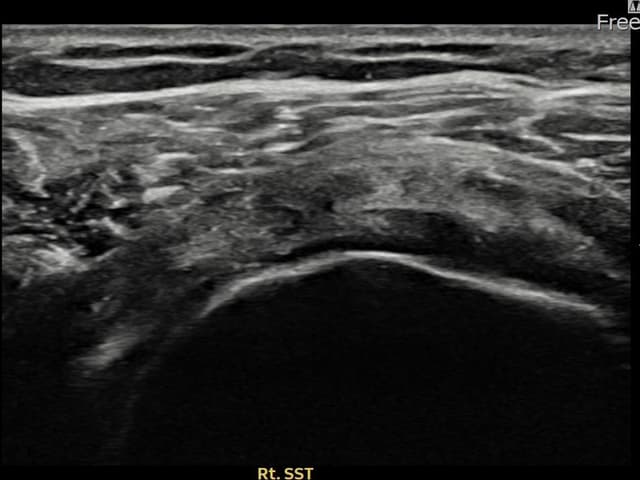

[촬영시기:21.09.27~21.10.07]

[석회분쇄흡입술] 우측 어깨의 야간 통증과 운동 제한으로 수개월간 고통받다 내원한 50세 남성 환자로, X-ray에서 극상근건 내 석회 침착이 확인되어 석회분쇄흡입술을 시행하였습니다.